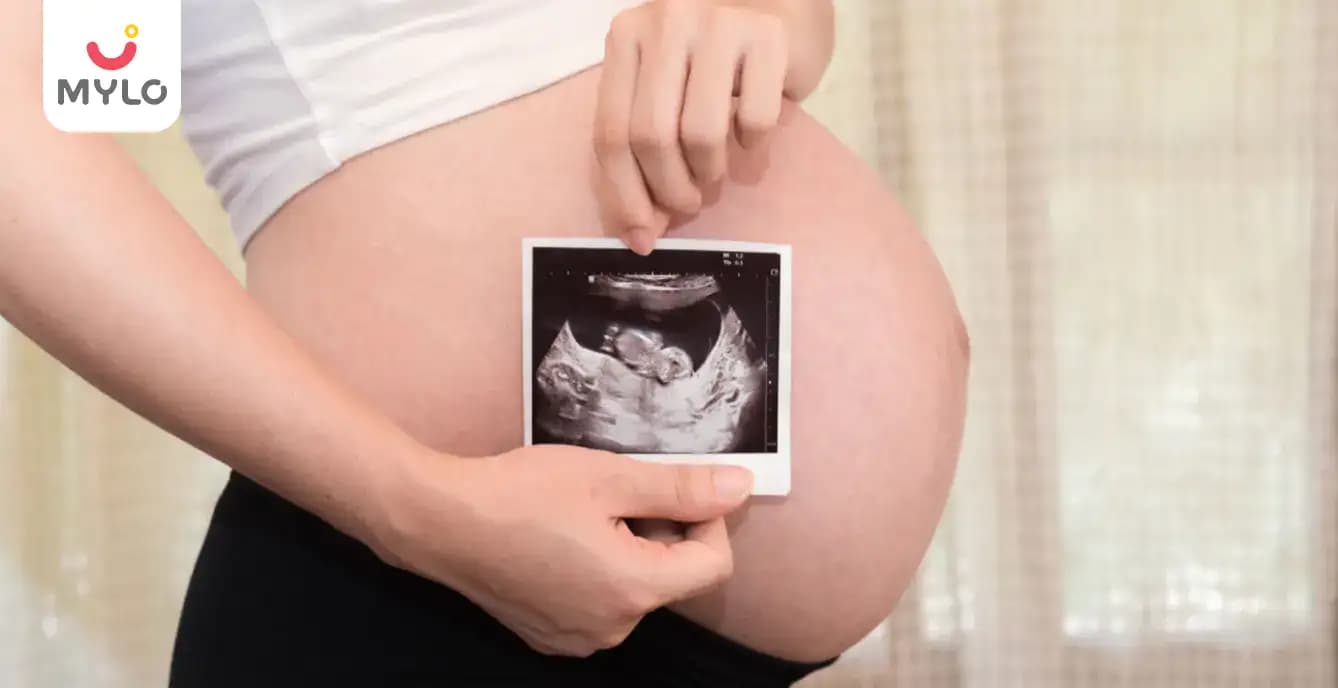

Scan & Tests can confirm your pregnancy and also monitor your baby’s development in the womb